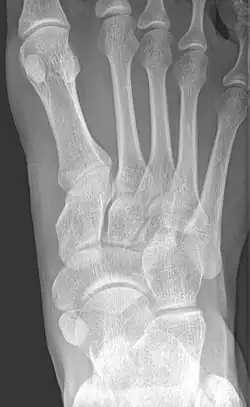

X-ray of the foot showing an accessory navicular bone

An accessory navicular bone is an accessory bone of the foot that occasionally develops abnormally in front of the ankle towards the inside of the foot. This bone may be present in approximately 2-14% of the general population and is usually asymptomatic.[1][2][3] When it is symptomatic, surgery may be necessary.

To diagnose accessory navicular syndrome, the foot and ankle surgeon will ask about symptoms and examine the foot, looking for skin irritation or swelling. The doctor may press on the bony prominence to assess the area for discomfort. Foot structure, muscle strength, joint motion and the way the patient walks may also be evaluated. X-rays are usually ordered to confirm the diagnosis. If there is ongoing pain or inflammation, an MRI or other advanced imaging tests may be used to further evaluate the condition.[5]